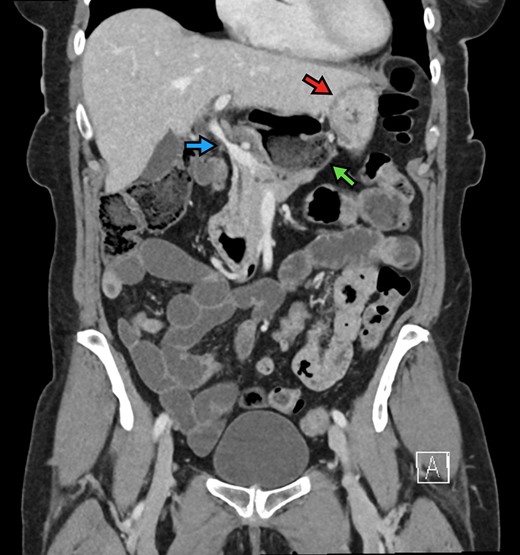

The patient is a 70-year-old woman who presented to the emergency department with acute-onset abdominal pain throughout her epigastrium for approximately 2 hours. The pain was constant and severe, extending across the bilateral upper quadrants. She had experienced pain like this once before within the past year which spontaneously resolved within 4 hours. The patient’s last oral intake was an hour before onset of the pain, and she denied any fevers, chills, nausea or vomiting. She was an otherwise healthy woman who took no medications and had no abdominal surgical history. On admission, vital signs were normal, with a heart rate in the 70’s. Although initially reported as tender by emergency department staff, after pain medication and intravenous fluids, examination by the surgical team revealed resolution of pain and a soft, non-tender abdomen. Lactic acid on presentation was 5.0 mmol/l, and her white blood cell count was 9600 µl−1, with the remainder of her laboratory values within normal limits. She underwent a computed tomography scan which demonstrated herniation of her cecum through the FoW, causing compression of the inferior vena cava (IVC) and portal vein (Figures 1–3).

Coronal view demonstrating FoW measurement and herniated contents. The stomach is demonstrated by the red arrow. The FoW is shown to be dilated at 4.4 cm.